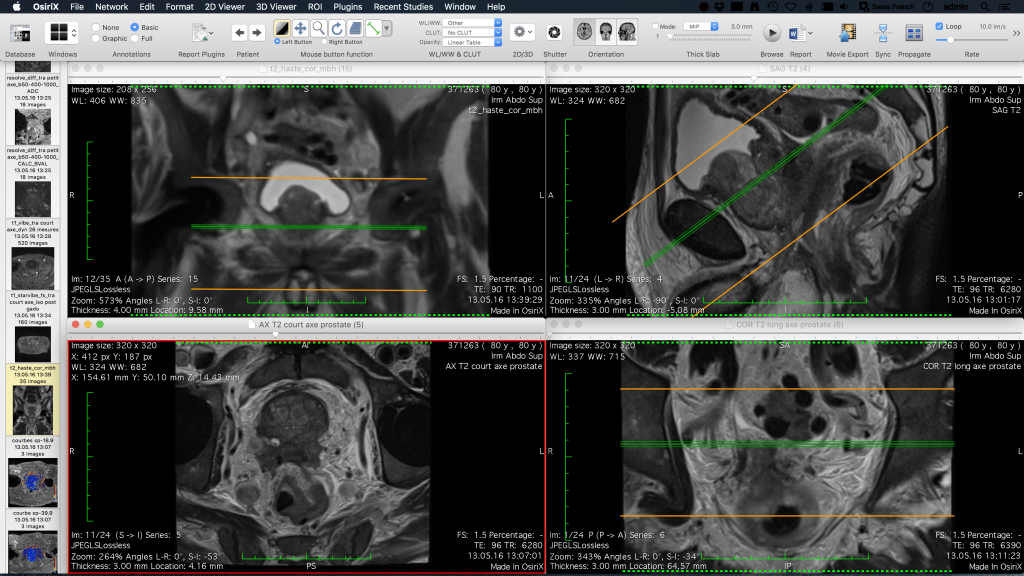

OsiriX MD, DICOM görüntüleri görüntülemek için sezgisel bir arayüz içerir. Retina ekran desteği ile en iyi renderleme için yüksek kaliteli enterpolasyonu destekler.

Çizgiler, çokgenler, 3B top gibi görüntülere Anahtar Görüntüler ve İlgi Alanları (ROI’ler) kolayca ekleyebilir ve bunları veritabanına kaydedebilirsiniz.

Birden çok ekran desteğiyle ‘Askı Protokolleri’ni tanımlayabilirsiniz.